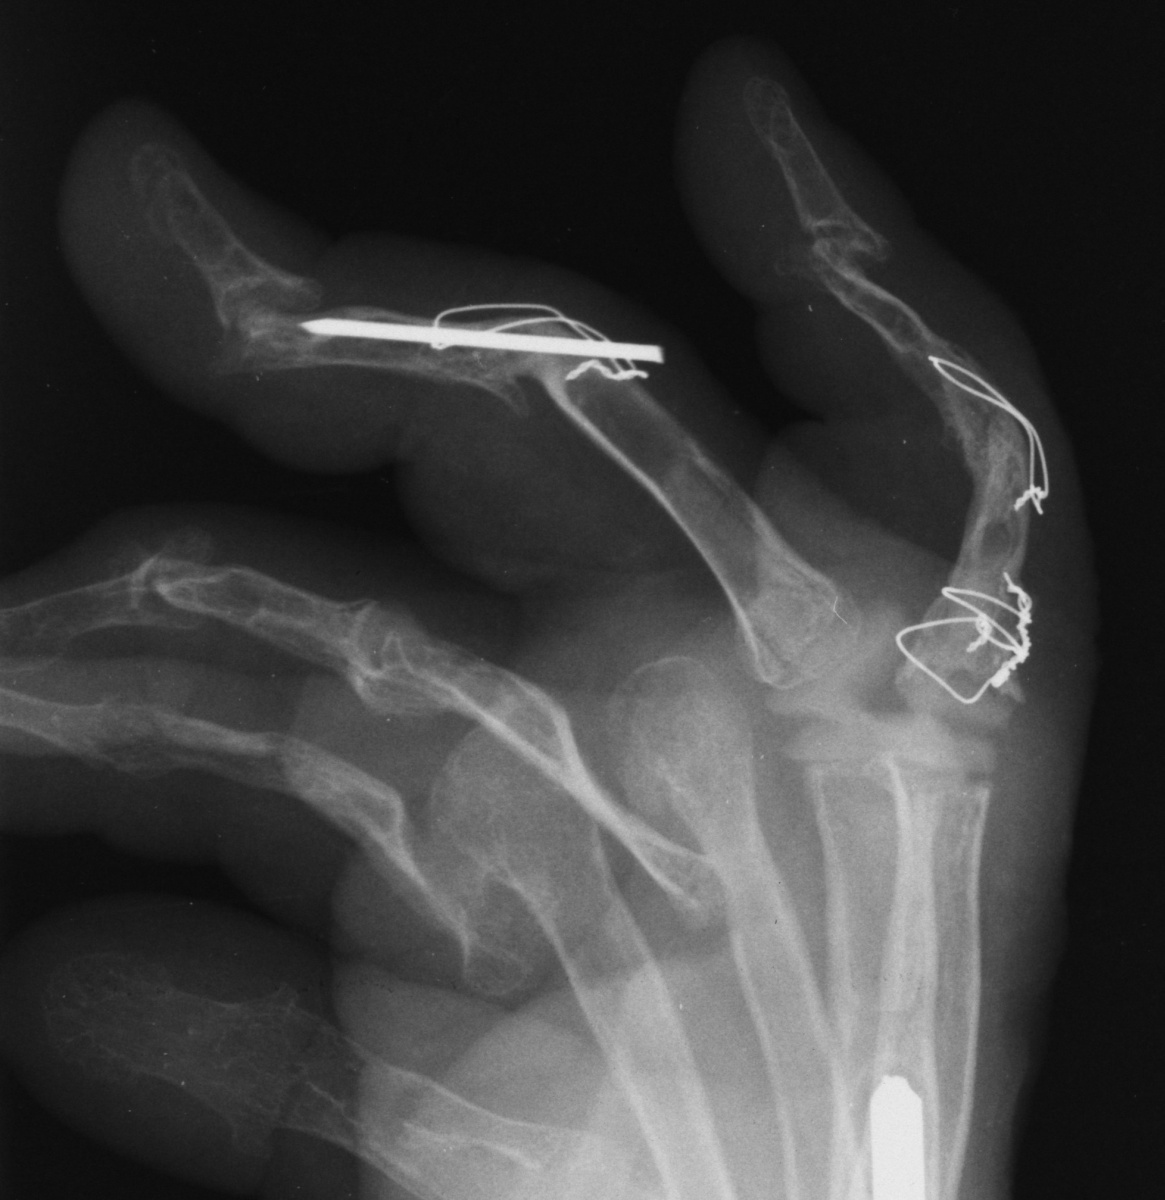

Her greatest desire was pinch reconstruction. This was approached in two stages: wrist fusion, implant removal and fusion of the index and middle PIP joints, followed by index and middle MCP arthroplasties. There are several alternative approaches, including index MCP fusion and revision PIP arthroplasties.

Below are xrays after the first set of reconstructions.

For the second stage of her reconstruction, the index proximal phalanx did not have adequate dorsal cortex to support an implant arthroplasty, and bone graft from the metacarpal head was used to reconstruct this.